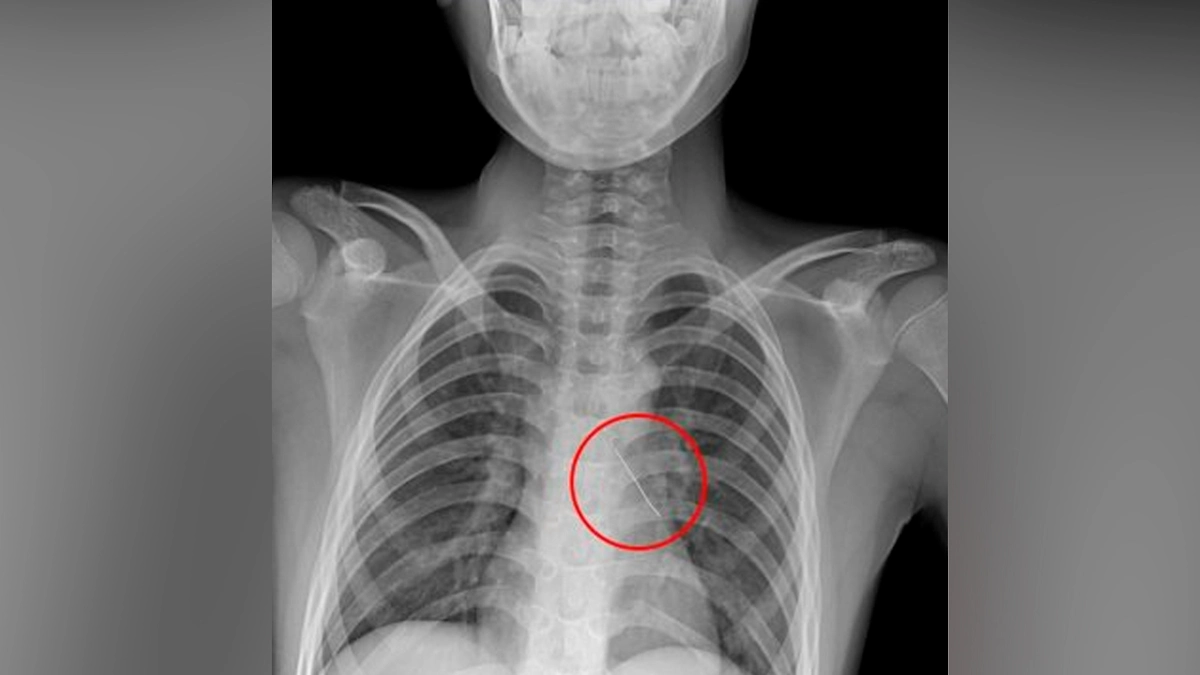

Врачи Российской детской клинической больницы (РДКБ) Минздрава России спасли 11-летнего мальчика, вдохнувшего булавку. Ребёнка экстренно доставили бортом санавиации из Калининградской области — он мог говорить только шёпотом и жаловался на сильную боль в груди, сообщили в клинике.

Рентген показал: изогнутая булавка находится в области нижней доли левого бронха и уже пронзила его стенку. Торакальные хирурги под визуальным контролем аккуратно извлекли инородное тело оптическими щипцами за колпачок. Удалось минимизировать кровотечение — оно остановилось самостоятельно.